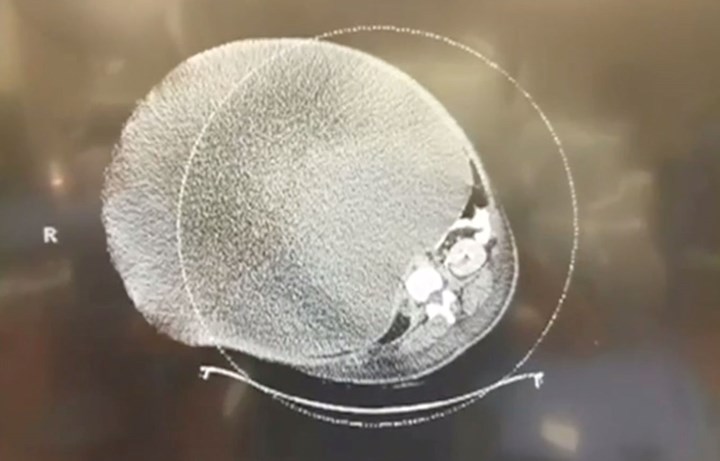

gif_animation アメリカ・ペンシルバニア州にて、卵巣に腫瘍ができ膨らんでいく病気、”卵巣嚢腫” を気付かずに患っていた女性。およそ16年の間肥大し続けた嚢胞は、病院で除去された際には約65kgの重さにまで成長していたそう。手術前~手術後まで。[6]images